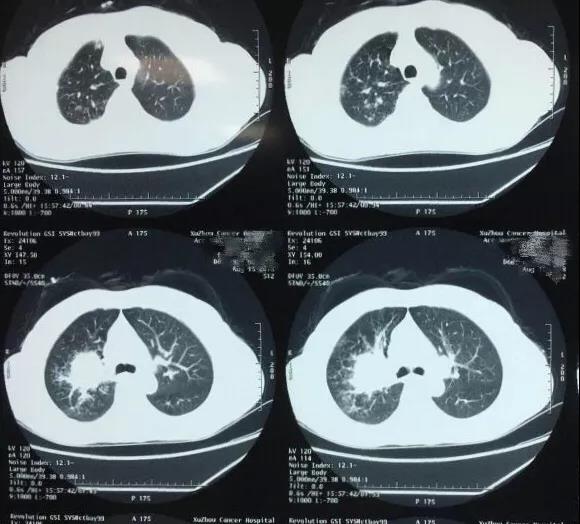

家住新沂的馮女士,近半年來總是咳嗽、咳痰,反反複複。一個禮拜前,馮女士的咳嗽突然加重,在咳痰中發(fā)現血絲,她的家人立即陪她前往當地醫院進(jìn)行檢查。經(jīng)檢查發(fā)現馮女士肺葉有結節,爲了進(jìn)一步确診,馮女士來到了徐州市腫瘤醫院。我院副院長(cháng)、胸外科主任侯予龍博士接診後(hòu),經(jīng)詢問病情發(fā)現患者符合肺癌臨床表現,遂讓其進(jìn)行了肺部穿刺。經(jīng)穿刺檢查确診,患者爲肺癌中期。

于是,侯予龍博士立即對(duì)馮女士展開(kāi)了進(jìn)一步全身腫瘤排查,檢查顯示馮女士左肺上葉與右肺上葉皆有病竈,左側上葉病竈較爲典型,右肺稍小。病人患慢性肺氣管炎、慢性肺氣腫、肥胖症,且心肺功能(néng)非常差,若同期進(jìn)入雙側胸腔手術,手術時(shí)間較長(cháng)、風險也會(huì)增加。結合年齡與身體因素,綜合評定後(hòu),侯予龍博士團隊建議患者,右肺随診觀察,先處理左側病竈,進(jìn)行“單孔胸腔鏡左上肺癌根治手術”。